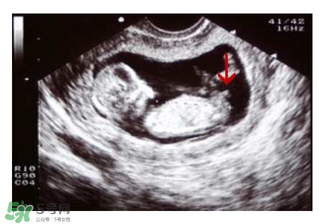

如果媽媽是孕晚期,也可以看B超圖,對著你的,一般是女寶寶,背著的,一般是男寶寶。

四維彩超看性別

四維彩超看胎兒性別準確嗎?四維超聲同其它超聲檢查相比,可以實時觀察人體內(nèi)部器官的動態(tài)運動,也能準確地分辨出胎兒的性別。雖然四維彩超能夠看清胎兒的性別,但在檢查過程中,為了避免透露胎兒的性別,醫(yī)生會主動的回避胎兒的性別特征以及下半身,同時,在后期制作光盤時,也會將可能泄露胎兒性別的部分進行處理。